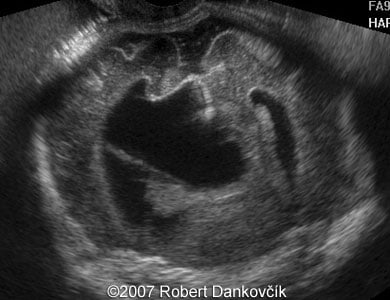

Images 3, 4: 2D sonography; 32 week of pregnancy; coronal planes through the fetal skull showing dilated lateral ventricles and interhemispheric cyst extending to the right.

3

4